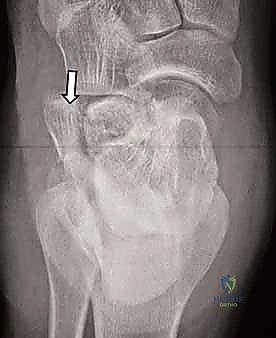

- التصوير بالأشعة السينية (X-rays): لأخذ فكرة أولية عن الكسر (زوايا بوهلر وجيسان - Bohler’s and Gissane’s angles).

- الأشعة المقطعية (CT Scan): وهي الخطوة الأهم والأكثر حيوية. توفر الأشعة المقطعية صوراً ثلاثية الأبعاد وتقاطعاً دقيقاً للكسر، مما يسمح بتصنيف الكسر (نظام ساندرز - Sanders Classification) وتحديد عدد الشظايا العظمية ومدى انزياحها داخل المفصل. بناءً على هذه الأشعة، يضع الدكتور هطيف خطته الجراحية الدقيقة.